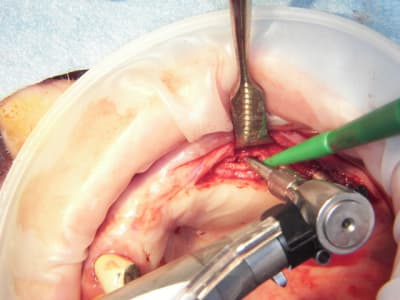

et puis alors??? on a un confrère qui s'éclate dans son travail et qui nous communique sa joie, en plus de photos qui nous apprennent beaucoup sur sa technique....c'est mieux que des posts du genre "j'en ai mare" ou " je flippe" ou encore "donnez moi une corde pour que je me pende..." , non???

pxav fait partie de ceux là...il nous en à fait à plusieurs reprises la démonstration avec ses techniques d'expansion osseuses extrêmement intéressantes...

15/07/2009 à 21h13

Pas cool le début de semaine.

1 patient trompé d'heure, reporté.

Deuxième cas je n'ai fait qu'un coté car le papy fatiguait (pas moi, le patient)

Pose d'implant court ce qui n'est pas ma tasse de thé, mais il ne faut pas mourir idiot, alors.

Un 103.4, un 6.5x4.6, un 8x4.6 et un 8x3.4

Première pour moi avec le nouvel Axiom d'Anthogyr.

Je n'étais pas sur de pouvoir utiliser la technique avec implant lisses, mais si.

Implants légèrement coniques, autoforants, outils trilobé et non pas 8 pans creux.

Pas eu de problèmes particuliers, il faut attendre pour le résultat.

Seul point il faut faire attention au vissage qui conditionne la position du cône morse.

Globalement j'ai bien aimé, même si je n'ai pas été aussi fabuleusement génial que d'ab dans la réalisation..........

Merci pour cette expérience partagée. Belles photos. Merci aussi d'avoir l'honnêteté de présenter un cas qui ,s'il paraît franchement parfait sur les photos de chir, l'est un poil moins sur la pano (mais c'est qu'une pano). De toute façon avec une expérience comme la tienne la gestion prothétique se fera sans doute sans trop de soucis.